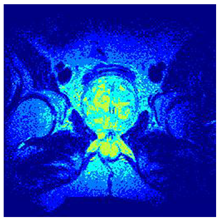

| Image | nt = 3 | nt = 4 | nt = 5 | nt = 8 |

|---|---|---|---|---|

| 1 | ![]() | ![]() | ![]() | ![]() |

| 2 | ![]() | ![]() | ![]() | ![]() |

| 3 | ![]() | ![]() | ![]() | ![]() |

| 4 | ![]() | ![]() | ![]() | ![]() |

| 5 | ![]() | ![]() | ![]() | ![]() |

| 6 | ![]() | ![]() | ![]() | ![]() |

| 7 | ![]() | ![]() | ![]() | ![]() |

| 8 | ![]() | ![]() | ![]() | ![]() |

| 9 | ![]() | ![]() | ![]() | ![]() |

| 10 | ![]() | ![]() | ![]() | ![]() |

| 11 | ![]() | ![]() | ![]() | ![]() |